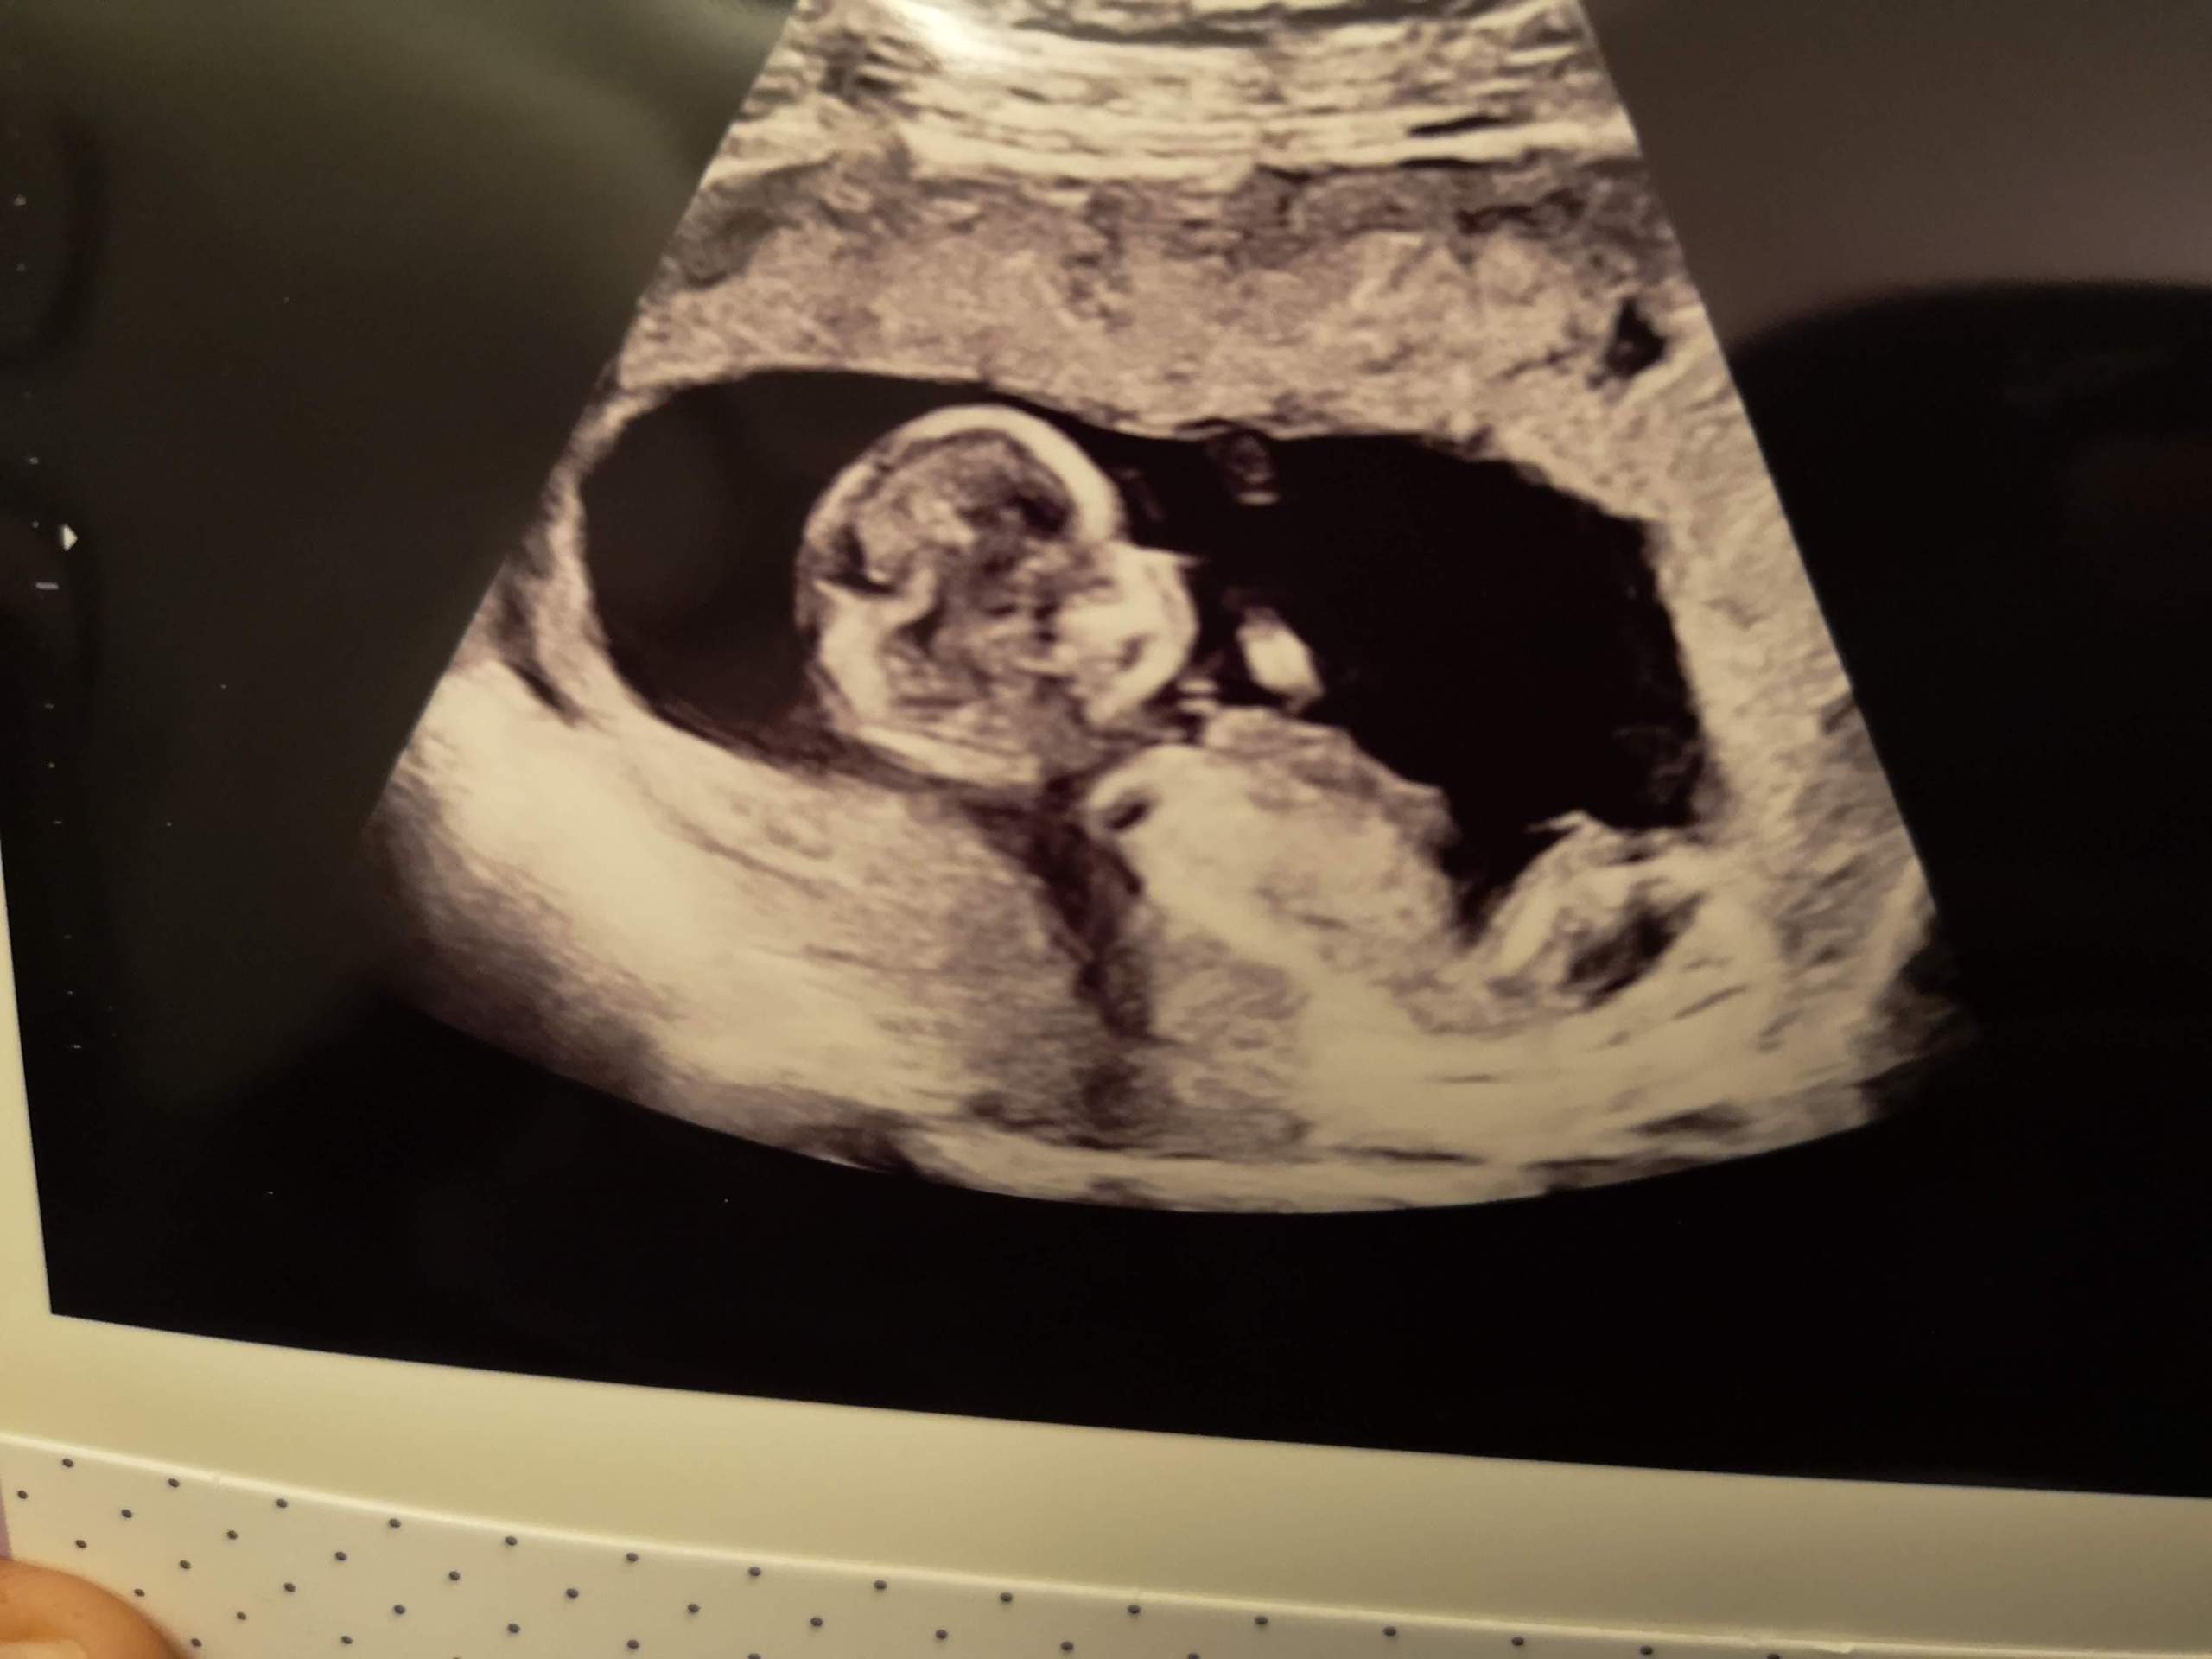

Bin ich schwanger? Erste Anzeichen einer Schwangerschaft 24Schwanger.de. Fetten Ihre Haare besonders schnell nach, und ist Ihre Haut unrein, könnten Sie mit einem Mädchen schwanger sein Frage, ob es ein Junge oder ein Mädchen wird, ist nicht nur spannend, sondern auch ein ganz besonderer Meilenstein auf dem Weg zur Elternschaft